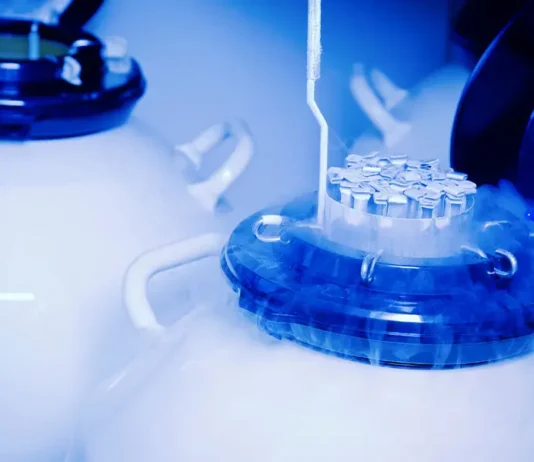

What Do You Mean By Clinical Research?

Clinical research and pharmaceutical licensing are a part of social healthcare science that decides the security and viability (adequacy) of drugs, devices, indicative items...